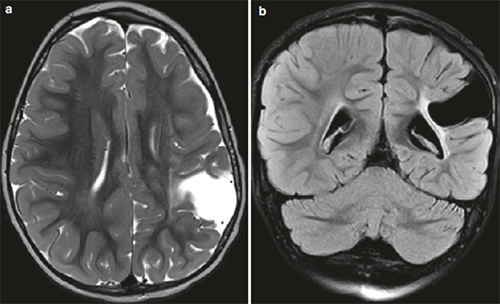

导致脑瘫的非进行性脑损伤病因,包括(1)发育不成熟的大脑(产前、产时或产后)、先天性发育缺陷(畸形、宫内感染) ;(2)获得性( 早产、低出生体重、窒息、缺氧缺血性脑病、核黄疸、外伤、感染);(3)脑瘫患儿出生时常常有早产或缺氧病史、以及感染、创伤等造成的脑损伤。常见的影像表现如下:

皮层区域性梗死